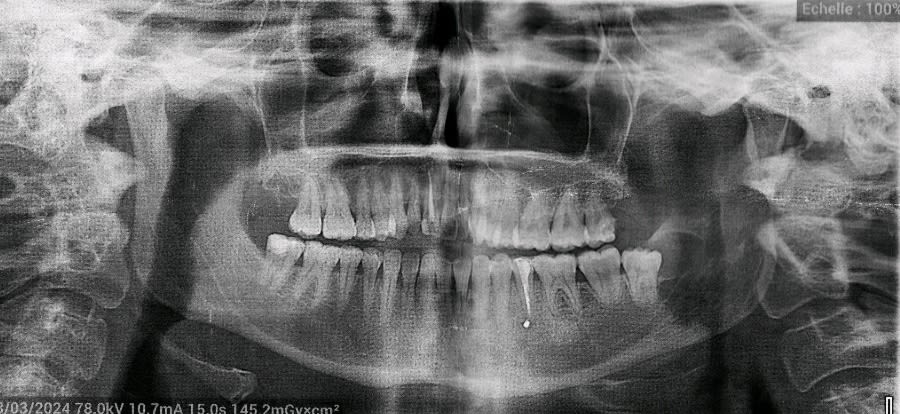

On me passe les antibios en IV, on me fait une prise de sang ( neutrophiles à 12 000 mais CRP normale) et je file voir le stomato des urgences. Il me fait un panorex (que je joins à mon message) et me dit que la douleur vient de 2 choses :

- Un morceau de "pâte" est passé dans la gencive lors du traitement définitif entraînant une inflammation (on voit la petite tâche blanche sur le panorex).

2.Retraitement canalaire. La pano n est pas précise, car l obturation semble manquer de compaction. Racine bifide ? Mais faudrait la rétro alvéolaire. Tout est supposition.

La radio fournie ici est inexploitable.

Bizarre, on ne distingue pas de couronne sur 35 sur la pano de mauvaise qualité.

Concernant la couronne, le panorex a été fait après la pause de la couronne aux urgences je ne sais pas pourquoi elle n'apparaît pas ...

En regardant de plus près il y a aussi la 28 qui est bien suspecte.